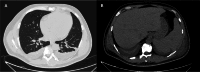

Malaria, caused by Plasmodium falciparum (PF), can lead to severe liver dysfunction and hyperbilirubinemia, worsening the prognosis. A 53-year-old male patient with malaria-related liver dysfunction and severe hyperbilirubinemia was treated with extracorporeal hemoadsorption (EHA) with the CytoSorb® filter (CytoSorbents, Monmouth Junction, NJ), marking a turning point in his treatment. This filter, by removing inflammatory mediators and bilirubin, significantly reduced bilirubin levels and improved the patient's clinical condition. This intervention facilitated a bridging therapy, improving symptoms and preventing organ damage during antimalarial treatment. CytoSorb® in EHA shows promise in treating malaria-induced liver dysfunction, suggesting the need for further research on its broader clinical application.